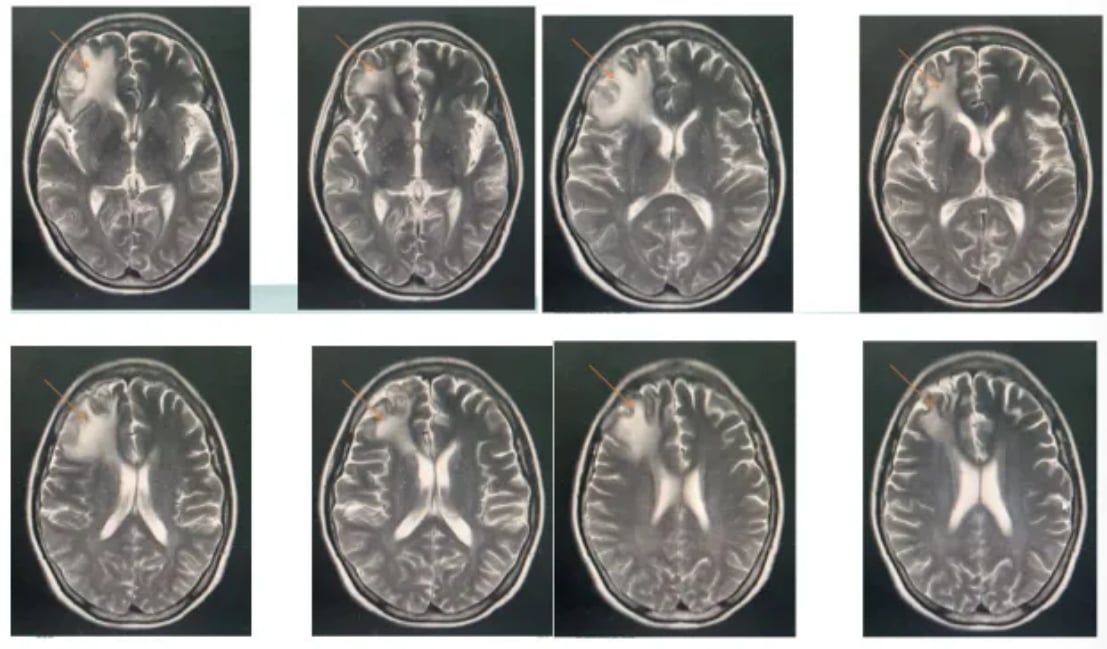

由于患者无法再次进行放疗,医疗团队决定采用以替尼泊苷为核心的联合化疗方案。具体用药包括:利妥昔单抗、替尼泊苷、异环磷酰胺、顺铂和地塞米松。经过3个疗程的治疗后,影像学评估显示患者达到了部分缓解(PR),颅内病灶明显缩小,病情得到有效控制。

尽管后续因新冠感染暂停治疗一个月,但患者病情依然稳定,显示出该方案带来的持续获益。这一成功案例表明,替尼泊苷联合化疗对于HD-MTX治疗失败的年轻患者是一种有效的挽救治疗选择。